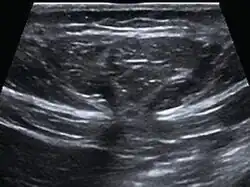

| Abdominal ultrasound of a midline epigastric hernia. | |

Ultrasonography is also used for diagnostic purposes.